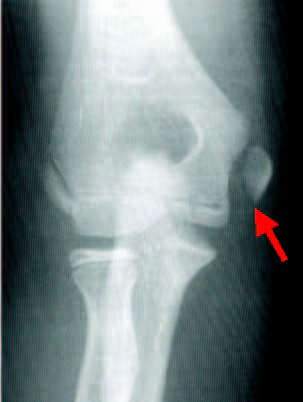

In younger athletes, their growth plates are the weak link and more prone to an injury. Growth plate injuries instead of ligament injury are more common in those athletes. Medial epicondylar avulsion fractures can happen instead of UCL tear. The sublime tubercle, where UCL inserts on ulna, can also avulse. In addition to valgus stress to the medial part of the elbow, the lateral side of the joint is under compressive force. This force can also cause an injury to the lateral side such as OCD (osteochondritis dessecans).

| X-ray of medial epicondylar avulsion fracture |